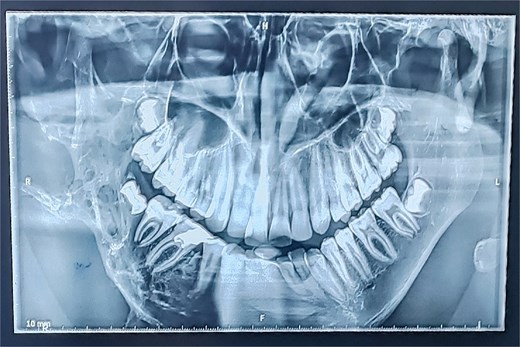

Panoramic radiography showed a well-defined radiolucent lesion involving the right mandibular angle and ramus. Coronal computed tomography (CT) scan in soft tissue window demonstrating a well-defined osteolytic mandibular lesion (12 × 9 × 14 cm) with cortical thinning (Figs 3 and 4).

Panoramic radiograph (OPT) revealing an extensive osteolytic lesion of the right hemimandible.